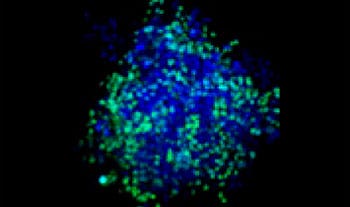

Making the spheroids transparent and imaging them with an FV3000 confocal laser scanning microscope enabled us to image the co-cultured cancer spheroids at depth. Staurosporine treatment increased the number of dead cells in a dose-dependent manner (Fig. 2*1). Three-dimensional analysis is required to determine which cells are dead and how many dead cells there are in a three-dimensional mass.

Figure 2. Drug response in co-culture spheroids

Figure 2. Drug response in co-culture spheroids*1